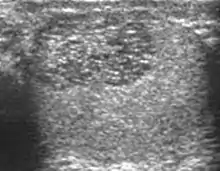

![]() Sonography of a normal testis. The normal testis presents as a structure having homogeneous, medium level, granular echotexture. The mediastinum testis appears as the

hyperechoic region located at the periphery of the testis as seen in this figure. | |

The normal adult testis is an ovoid structure measuring 3 cm in anterior-posterior dimension, 2–4 cm in width, and 3–5 cm in length. The weight of each testis normally ranges from 12.5 to 19 g. Both the sizes and weights of the testes normally decrease with age. At ultrasound, the normal testis has a homogeneous, medium-level, granular echotexture. The testicle is surrounded by a dense white fibrous capsule, the tunica albuginea, which is often not visualized in the absence of intrascrotal fluid. However, the tunica is often seen as an echogenic structure where it invaginates into the testis to form the mediastinum testis. In the testis, the seminiferous tubules converge to form the rete testes, which is located in the mediastinum testis. The rete testis connects to the epididymal head via the efferent ductules. The epididymis is located posterolateral to the testis and measures 6–7 cm in length. At sonography, the epididymis is normally iso- or slightly hyperechoic to the normal testis and its echo texture may be coarser. The head is the largest and most easily identified portion of the epididymis. It is located superolateral to the upper pole of the testicle and is often seen on paramedian views of the testis. The normal epididymal body and tail are smaller and more variable in position.